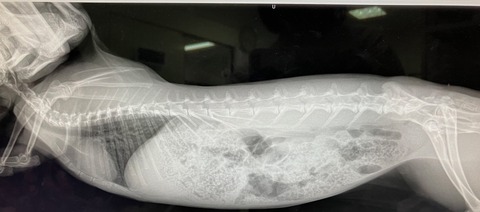

12月4日、ドナちゃん避妊手術しました。

※白血球の上昇などはストレス起因と判断できるレベル、と、

血小板は機械の誤作動による、顕微鏡で別途確認済

奥歯も問題なし。

術前の血液検査、レントゲン、いずれも問題ありません。